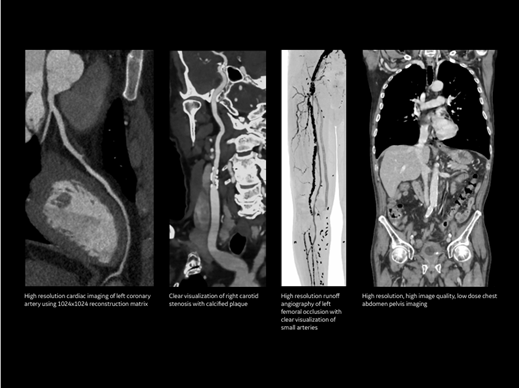

Công nghệ hình ảnh tiên tiến – chẩn đoán chính xác

Máy chụp cắt lớp GE Revolution Maxima được trang bị công nghệ thu nhận hình ảnh độ phân giải cao, cho phép bác sĩ quan sát rõ ràng nhiều cơ quan và hệ thống trong cơ thể như:

Nhờ chất lượng hình ảnh vượt trội, bác sĩ có thể phát hiện sớm các tổn thương nhỏ, hỗ trợ chẩn đoán chính xác nhiều bệnh lý phức tạp.